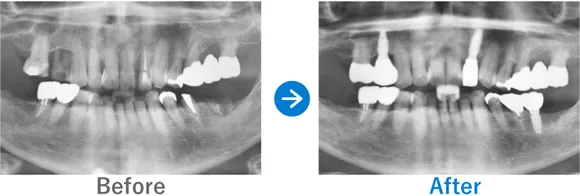

Case8

2度目のインプラント。定期メンテを欠かさず13年前のインプラントも状態良好

左下奥歯のブリッジの不良

インプラント5本:左上5・7、右上5・6(2012年)、左下5・6・7(2024年施術)、抜歯ソケットプリザベーション

3,092,800円(内訳:上顎(2012年):インプラント4本(京セラ)、保証5年/下顎(2024年):抜歯ソケットプリザベーション、インプラント3本(ストローマン)、ガイド、仮歯、セデーション、保証20年)

治療結果

下顎左奥のブリッジの歯は、内部が虫歯になっていました。また、根っこの周囲の骨もやせている状態だったため、ソケットプリザベーション(抜歯後すぐに骨吸収を抑える処置)をし、インプラントを3本埋入しました。

上顎左右奥のインプラントは2012年に施術されていますが、定期メンテナンスを欠かさずに受けてくださっていることもあり、13年経っても良好なコンディションを保てています。